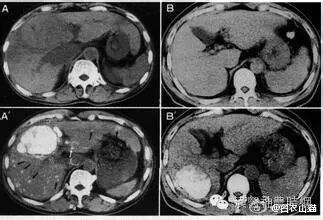

2.计算机X线体层扫描(CT)  CT是一种安全、无创伤、高分辨力的检查方法。对肝癌的定位诊断很有价值。CT能显示肿瘤的大小、位置、数目及与周围脏器和大血管的关系,可检出1cm左右的早期肝癌。并有助于了解是否伴发肝外转移,如肝门淋巴结,胰头后淋巴结等。结合增强扫描可以判断病变的性质,对肝癌与肝血管瘤的鉴别有较大的价值。平扫下肝癌多为低密度占位,边缘清晰或模糊,部分有包膜的肝癌可显示晕圈征。较大的肝癌可见更低密度的坏死区,少数肝癌可见钙化。增强扫描有滴注法、大剂量推注、推注加动态扫描等。

肝癌在动脉期尤以注药20s内强化最为明显,癌灶密度高于周围肝组织。30~40s后造影剂进入细胞间隙转入实质期,病灶又恢复为低密度,显示更为清晰。近将肝动脉造影与CT检查相结合,开展CT动脉造影(CTA)和CT动脉门脉造影(CTAP),对提高小肝癌的检出率有一定价值。也有人在CT检查前一周经肝动脉插管注入碘化油(lipiodo1),再做CT扫描,这种lipiodol-CT可检出0.5cm的小肝癌。对于<1cm的肝癌,Uchida报告US、CT、肝动脉造影和几种CT检查的分辨力为:US 63%、普通CT 12%、滴注法增强扫描65%、CTA 71%、CTAP 80%、lipiodol-CT 89%。

3.磁共振显像(MRI)  MRI在肝癌诊断中的作用日益受到重视,其诊断价值有超过CT的趋势。与CT相比其优点为:无电离辐射,能获得横断面、冠状面、矢状面3种图像,对肿瘤与肝内血管的关系显示更佳;对软组织的分辨力高;对肝癌与肝血管瘤、囊肿及局灶性结节性增生等良性病变的鉴别价值优于CT。国外报道MRI对大于2cm的肝癌的检出率为97.5%,小于2cm者为33.3%,检出最小的肝癌为1.5cm。近年有采用钆离子螯合剂作对比增强剂成像,提高了MRI对微小病灶的检出率,并有助于肿瘤性质的判断。

原发性肝癌在T1加权像上多为低信号占位,少数可为等信号或高信号,坏死液化信号更低;伴有出血或脂肪变性则局部呈高信号区;钙化表现为低信号。在T2加权像上,绝大多数肝癌表现为强度不均的高信号区,少数可呈等信号区;液化坏死区信号强度很高;钙化则为点状低信号。门静脉或肝静脉癌栓在T1加权和质子密度像上呈稍高的信号;在T2加权像上为较低的信号强度。假包膜在T1加权像表现为肿瘤周围的低信号带,在T2加权像上内层纤维组织为低信号带,外层丰富的受压的小血管或胆管则为高信号带。MRI T1加权像可显示清晰的肝脏血管解剖,对指导手术有很大的参考价值。